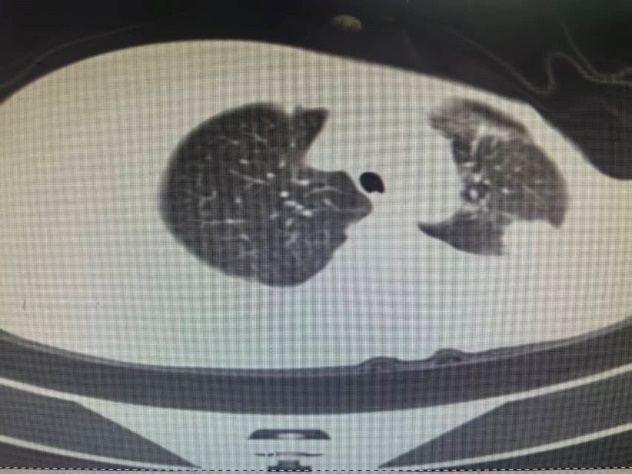

临床资料: 男性,45岁,CT发现双肺多发结节,较大者位于右肺中叶外侧段,直径约14mm。